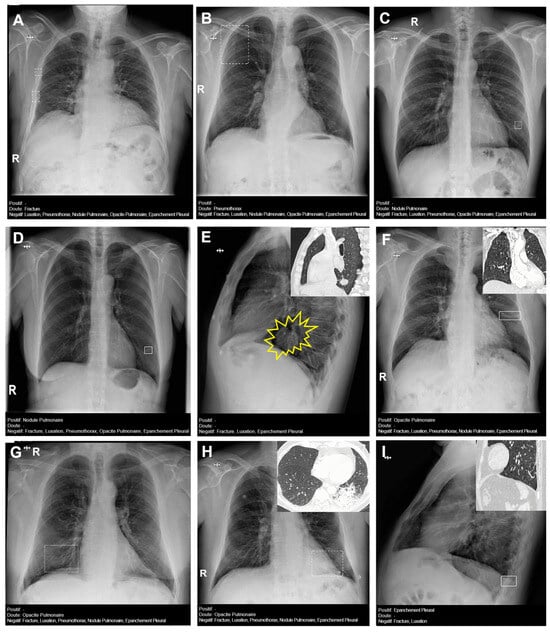

The prevalence of other variables included 16% for mediastinal abnormalities (cardiomegaly, hiatal hernia, widening of the superior mediastinum), 20% for surgical material (staples, metal valves, stents), and 20% for other pulmonary findings (pulmonary hyperinflation). Cardiomegaly was the most frequent finding (80%). Hyperinflation was found in only 7% (Figure 5 and Figure 6).

Figure 6. Chest radiographs with additional findings highlighted by red circles, arrows, or lines. (A) Hiatal hernia, (B) cardiomegaly, (C) widening of the superior mediastinum, (D) heart pacemaker, (E) pulmonary surgical material, (F) sternal surgical material, (G,H) pulmonary hyperinflation (G—flattening of the diaphragms and enlarged retrosternal space; H—enlarged retrocardiac spaces).